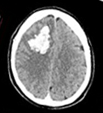

Ematoma

sottodurale acuto ed intraparenchimale |

Malformazione

Artero Venosa (MAV) |